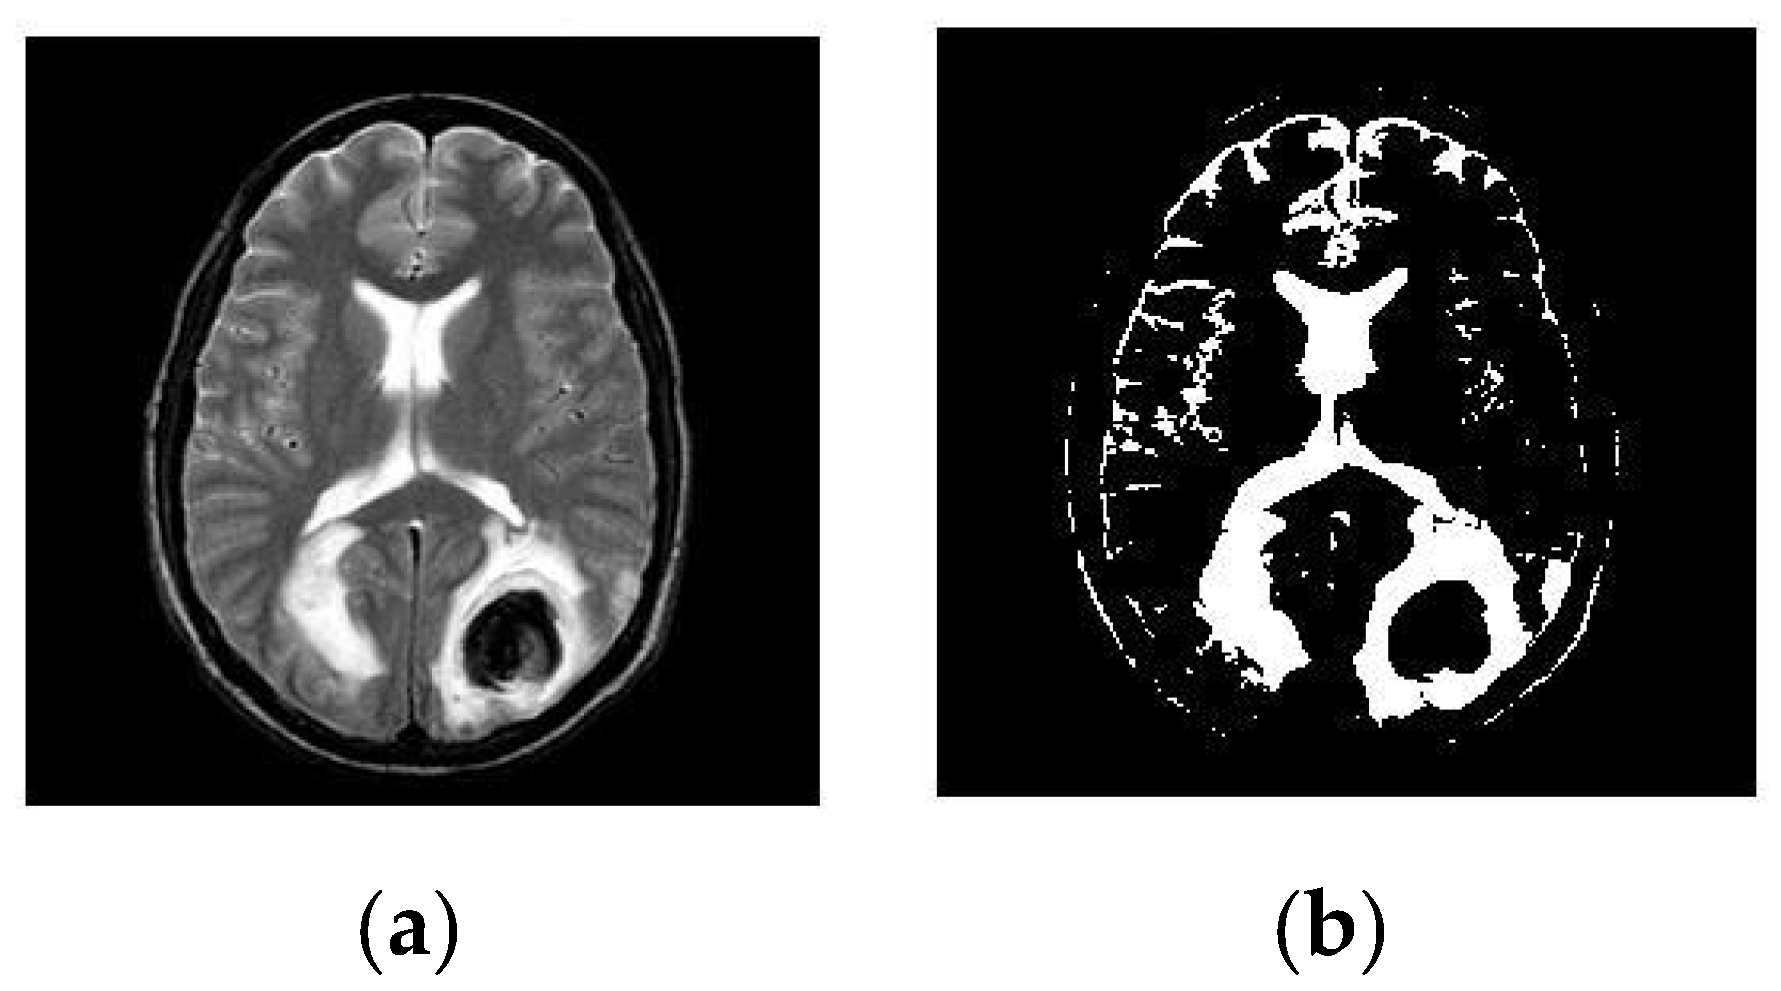

3.2. Segmentation

5.3. Result 3: Experiment with T-2 Weighted MRI Image Dataset

- (a)

- Classification of Abnormalities in T-2 Weighted Images

- (b)

- Tumor Classification for T-2 Weighted Images